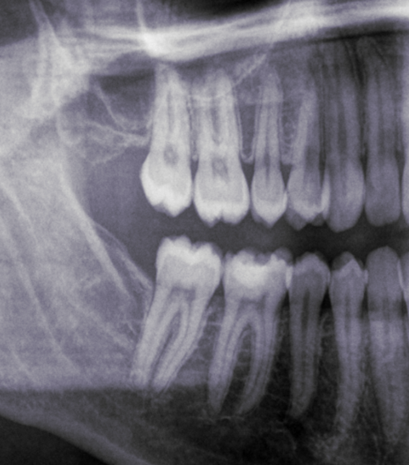

Look at these x-rays:

This patient was a female in her mid-30s. We will call her FA. As you can see, she only keeps her left wisdom teeth. At the age of 15, FA’s dentist wrongly diagnosed all her four wisdom teeth as impacted and recommended her to get them all out. FA was scheduled for two appointments: one to remove her right ones, and the other for the left ones.

Being 15 years old, I can imagine her wisdom teeth were still forming, deep in the bone. Maybe a big osteotomy (bone removal) was necessary to get to them. The issue of young teenagers (when not children) getting their wisdom teeth removed is also quite outrageous, but this article is long enough as it is already, so I won’t cover it here. The thing is that her post-operatory period was absolutely awful, so much so, that she refused to go get her remaining wisdom teeth removed.

Her case serves as a perfect illustration of three issues that I often denounce on this project: dentists failing to see that a wisdom tooth does have space to come in; dentists removing all four wisdom teeth automatically and without further reflection; and mutilations.

Her left wisdom teeth, also diagnosed as impacted back then, are obviously not impacted! Having examined her mouth, I can confirm they are perfect, ideally erupted and taking part in chewing like the normal teeth they are. Yet, they were diagnosed as impacted, with no place and problematic. This is nothing short of horrifying.

And I can very confidently say that her right molars were not impacted either, because of her wide retromolar spaces to the right (that is, the spaces behind her second molars), because we can be sure that her dentist was not able to properly diagnose impactions, and because of how ideally positioned and erupted her remaining wisdom teeth are. And no, she wasn’t having any kind of symptoms, discomfort or infections. Nor did she need the removal for any orthodontic or surgical reasons.

In a nutshell: she was mutilated.